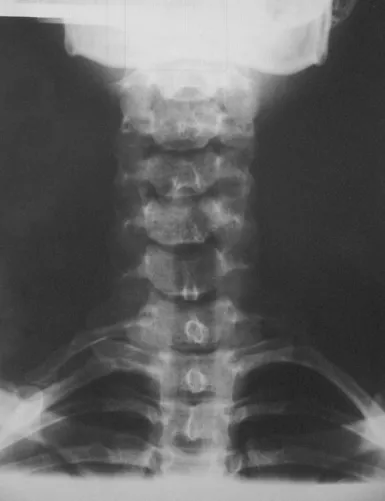

Nyaki borda Nyaki borda Kétoldali nyaki borda a hetes, egyoldali a hatos nyakcsigolyán. Kategória Diagnosztika Közzétéve: 2016. 04. 23. 14:49